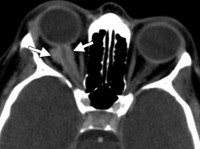

Диагностика менингиомы зрительного нерва включает в себя проведение визиометрии, тонометрии, офтальмоскопии, ультразвукового исследования, компьютерной томографии, магнитно-резонансной томографии. При помощи УЗИ можно охарактеризовать тип роста опухоли, степень прорастания в окружающие структуры, контуры новообразования. Преимуществом данной методики является возможность провести анализ в виде цветовой картограммы потоков сосудистой сети в режиме цветового допплеровского картирования. В среднем максимальная линейная скорость кровотока в сосудах составляет 13-15 см/с. МРТ показана пациентам со вторым типом роста опухоли или при дополнительной локализации патологического процесса в структурах головного мозга. КТ назначается при распространении менингиомы зрительного нерва за пределы глазницы. При проведении МРТ и КТ можно не только обнаружить новообразование, но и изучить его размер, структуру и распространенность.

Методом визиометрии при субдуральной менингиоме зрительного нерва уже на ранних стадиях определяется снижение остроты зрения. При втором типе роста данный признак наблюдается только на поздних этапах развития опухоли. Проведение тонометрии указывает на повышение внутриглазного давления (ВГД) только при большом размере новообразовании. На ранних стадиях процесса ВГД в пределах нормы (10-20 ). Диагностика субдуральной менингиомы зрительного нерва на начальных этапах развития затруднена в связи с незначительным увеличением диаметра оптического нерва. При эксцентричном росте (2 тип опухоли) необходимо дифференцировать менингиому от опухоли параневральной локализации иного происхождения.